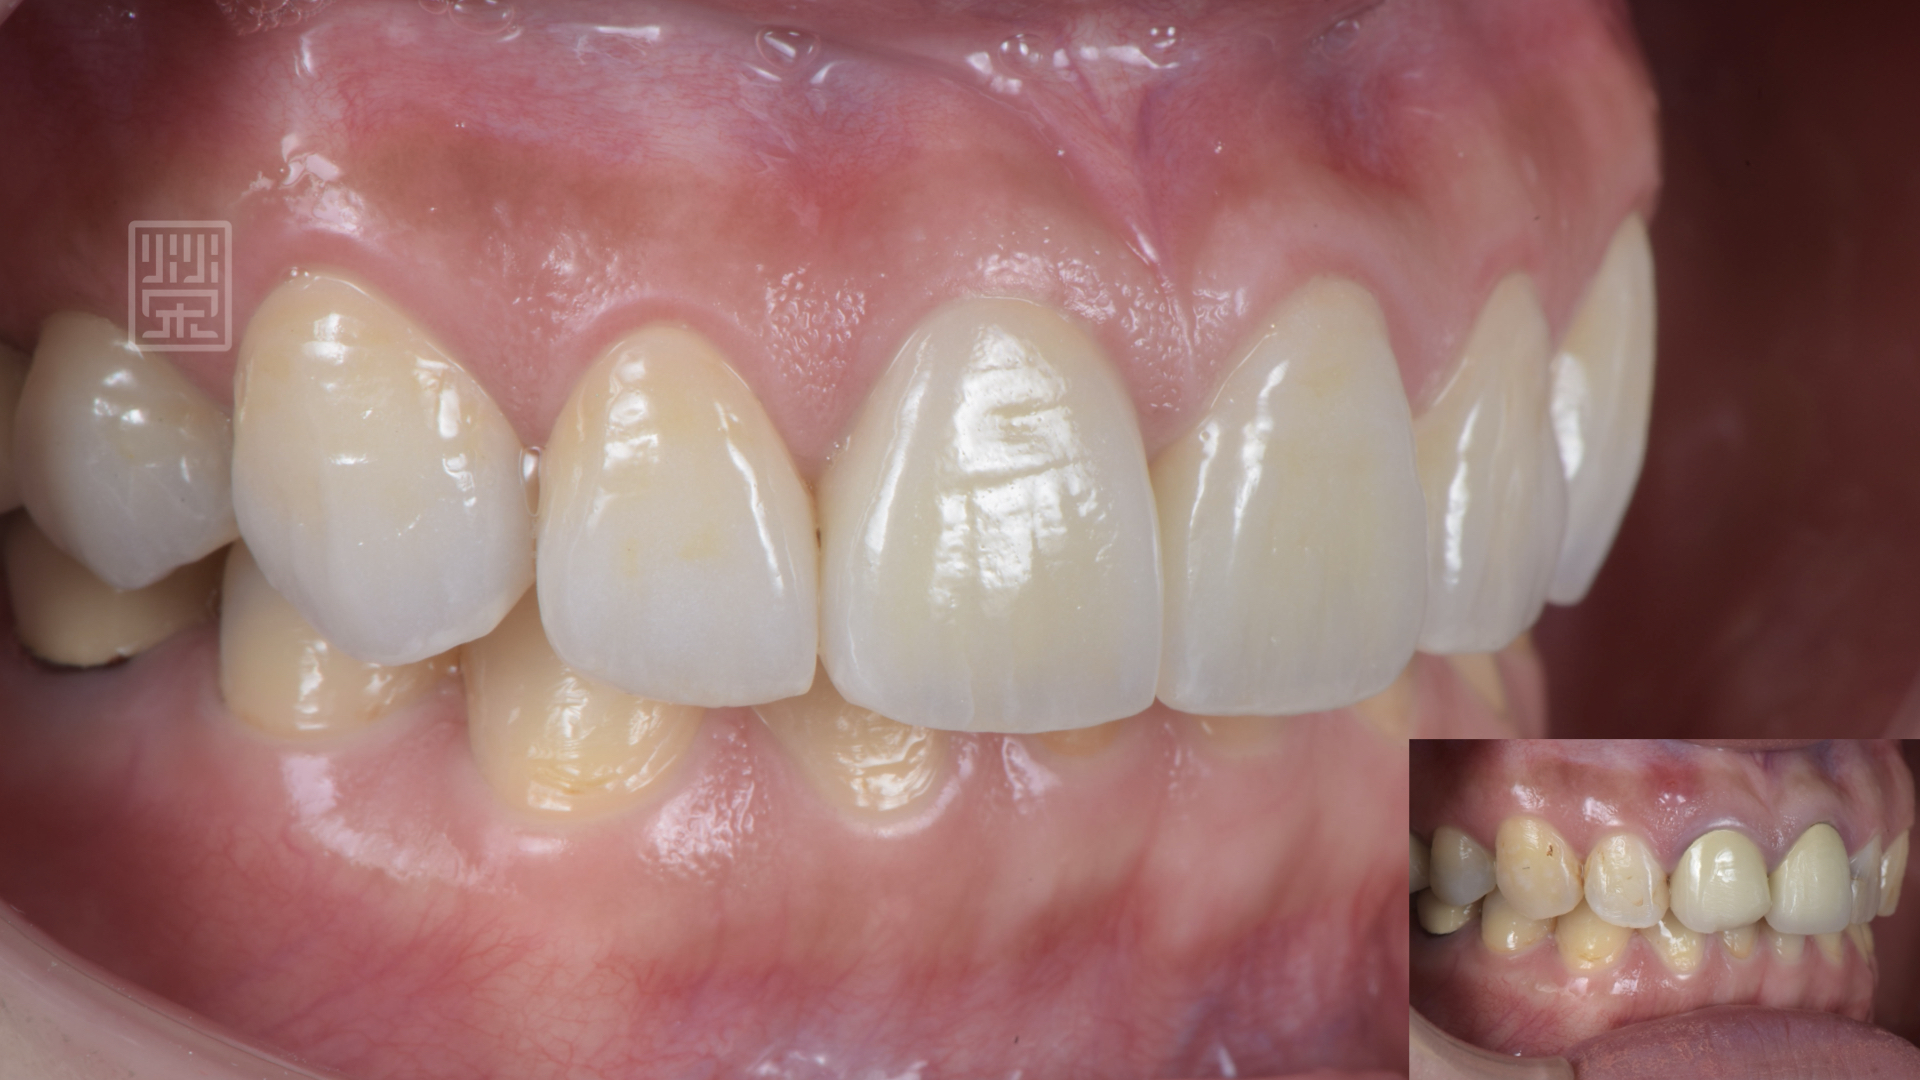

植牙、全瓷冠、全瓷貼片完成

貼片全瓷冠與笑容和諧